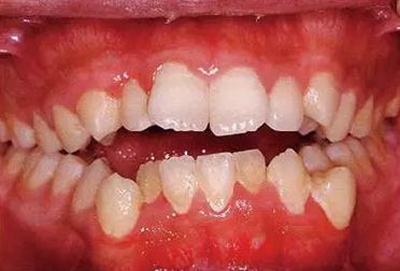

強(qiáng)化患牙齦炎的牙周組織

患牙齦炎的牙周組織是如何形成的?

患牙齦炎時(shí)牙齦腫脹并發(fā)紅。一般從牙間乳頭部開始擴(kuò)大到牙齦邊緣。齦溝滲出液增加,受刷牙等刺激容易出血。游離齦溝、step ring消失形成假性牙周袋,纖維性肥厚呈帶狀。下顎前牙舌側(cè)及上顎臼齒臉頰側(cè)等唾液腺開口部附近還可見發(fā)白的齦上牙石。